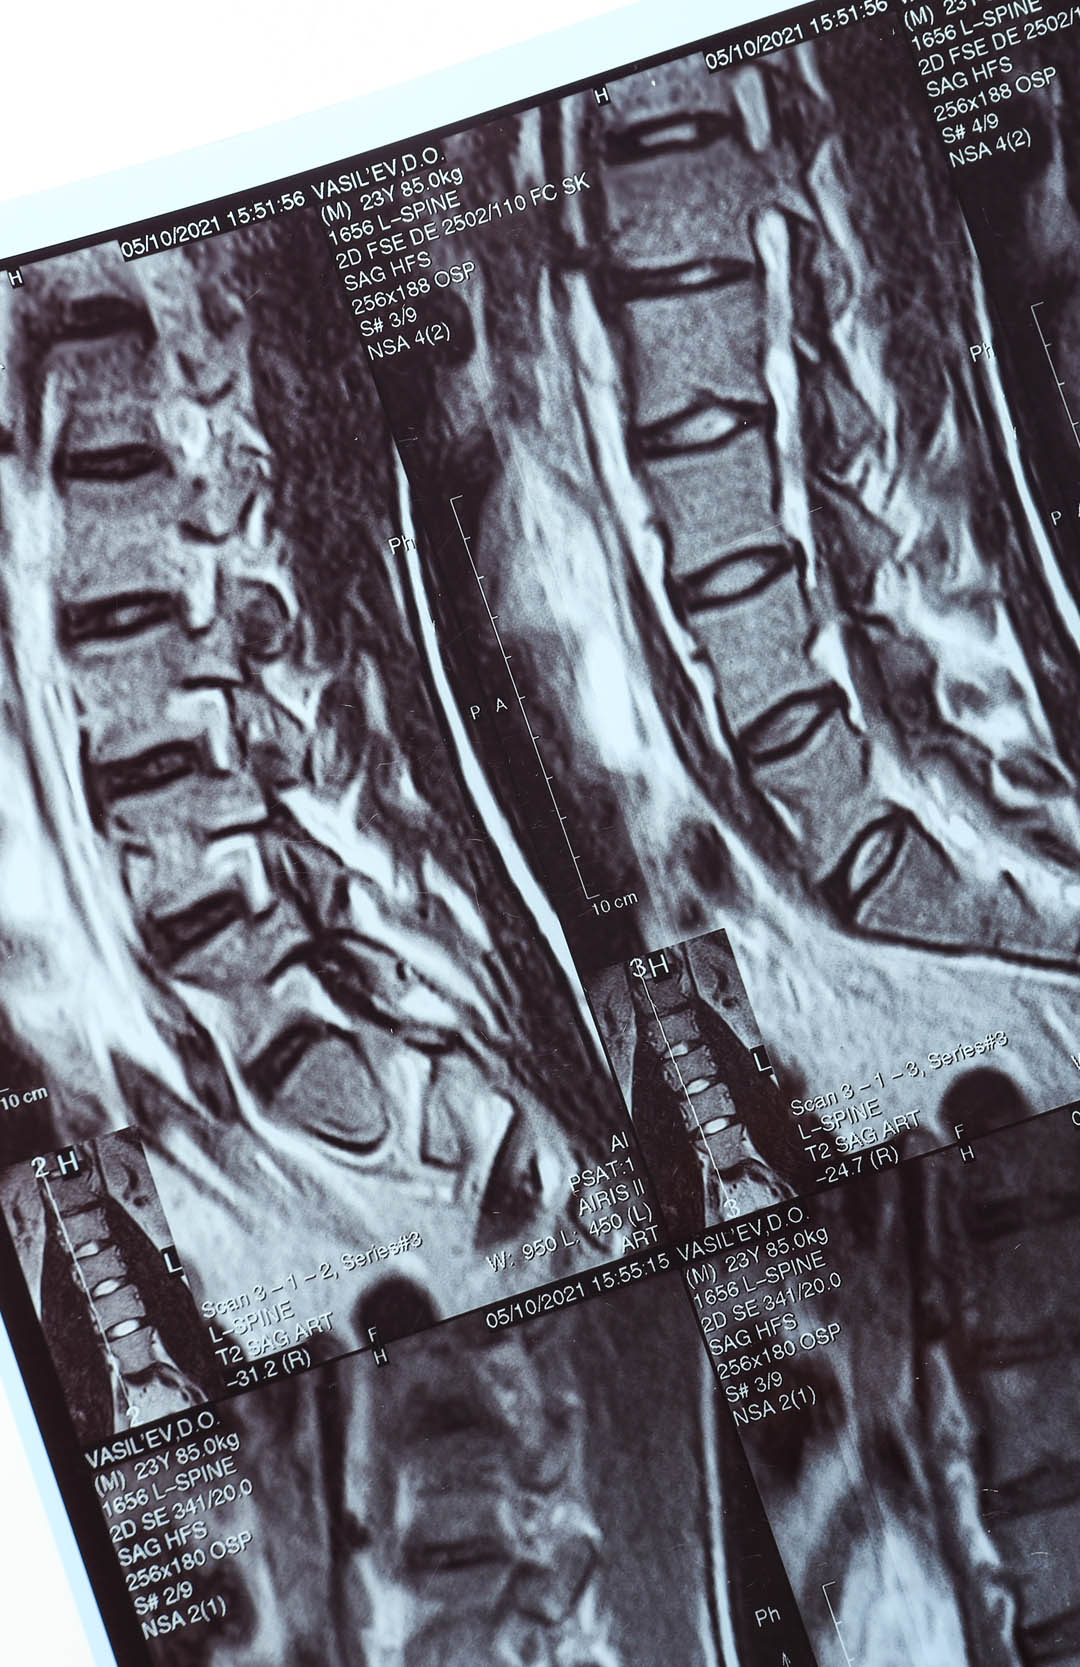

Ein modernes MRT ist für uns mehr als nur Bild­ge­bung, es ist die Grund­lage für fun­dierte Ent­schei­dungen. Wir machen Struk­turen, Gewebe und Ver­let­zungen sichtbar, die mit bloßem Auge oder klas­si­schen Unter­su­chungen nicht erkennbar sind. Ob Mus­keln, Sehnen, Bänder, Gelenke oder Wir­bel­säule – unsere hoch­auf­lö­sende Magnet­re­so­nanz­to­mo­gra­phie ermög­licht eine exakte Dia­gno­se­stel­lung ohne Strah­len­be­las­tung. So erkennen wir Ursa­chen statt Sym­ptome. Und schaffen die Basis für gezielte, wirk­same The­ra­pien.

Die Magnet­re­so­nanz­to­mo­gra­phie (MRT) ermög­licht eine hoch­auf­lö­sende, strah­len­freie Bild­ge­bung zur gezielten Abklä­rung der jewei­ligen medi­zi­ni­schen Fra­ge­stel­lung.